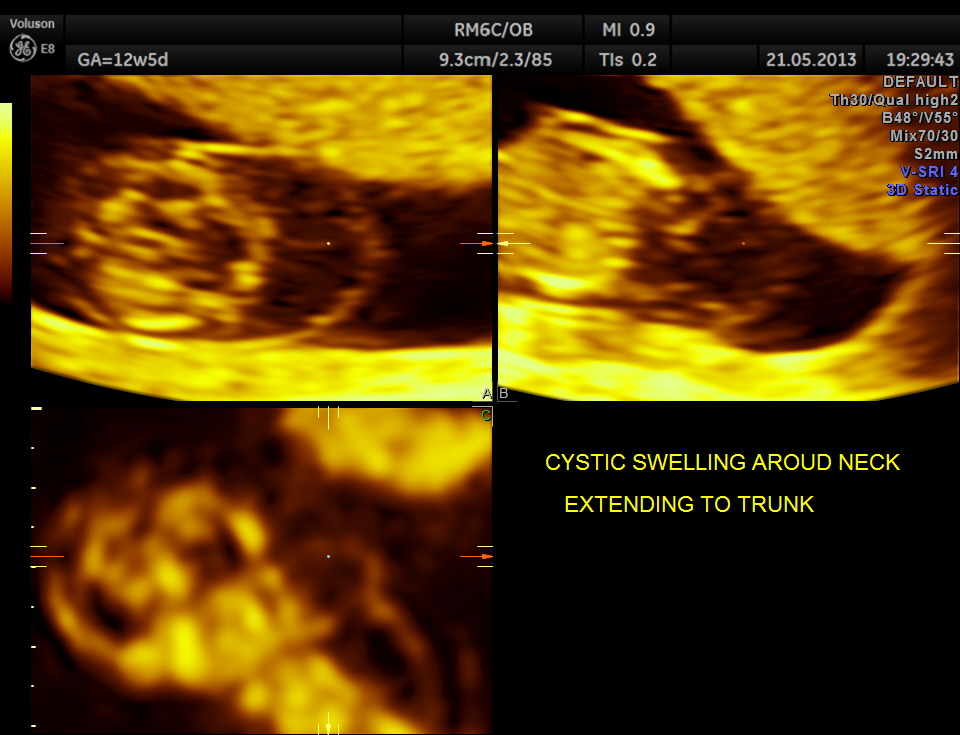

the following are some reconstructed images.

The diagnosis offered was cystic hygroma .

Cystic hygroma colli probably represent the most common cause for a neck mass detected prenatally. Other neck masses detectable ultrasonically include cervical meningomyelocele, hemangioma, teratoma, goiter, sarcoma, and metastatic adenopathy. Occasionally, a large cephalocele may mimic a neck mass. In most of these rare cases, polyhydramnios, hydrops fetalis, or other clinical features signal a careful search of the fetal neck.

1. Is the mass unilateral or bilateral, posterior or anterior ?

* most bilateral posterior masses are cystic hygroma colli, especially multicystic masses with a midline septation.